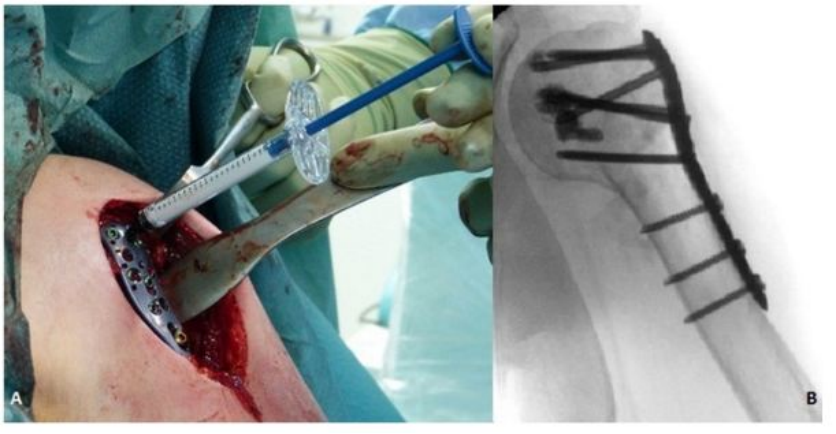

但是,锁定钢板的应用仍有许多问题值得注意,锁定钢板的刚度过高,导致在一定载荷下,骨折块间的微动过小,抑制了骨痂的形成,从而影响骨折的二期愈合,甚至骨不愈合[10]。此外,高度粉碎性骨折残存的骨折块间隙或对侧皮质缺损均会增加骨折部位弯曲的风险,最终导致内固定失败。因此,在使用锁定钢板时,应尽可能减少骨折块之间的间隙[11];此外还应选用较长的锁定钢板,较少数量的螺钉和较宽的钢板跨度,以使应力分散[12]。

锁定钢板在承受轴向载荷时会发生微小弯曲,由此产生的骨折块间微动是不对称的,越靠近钢板侧的皮质,骨折块间微动越小,越不利于骨痂生成,最终导致骨痂形成的不对称。为了克服锁定钢板的这些缺陷,近年来也出现许多新的技术,例如“对侧皮质锁定技术”和“近侧皮质开槽技术”,其目的均是为了降低锁定钢板的刚度,减少因刚度过高导致的不愈合[13] [14] [15]。“对侧皮质锁定技术”为了增加弹性和防止对侧皮质承受的应力过大,其使用的锁定螺钉直径较传统螺钉小,因而可能会过早的发生疲劳断裂[16]。而“近侧皮质开槽技术”不需要使用特制的锁定螺钉,但是近侧皮质需提前开槽。尽管这些新技术的效果已经得到了生物力学研究的证实,但是由于缺乏高级别的临床研究证据,目前其临床应用仍受到许多限制。

丙烯酸骨水泥在骨科手术中发挥着重要作用,其中聚甲基丙烯酸甲酯(PMMA)已从最初的眼科和牙科领域,扩展至骨科领域,并广泛地应用于假体内植物的固定、肿瘤和椎体骨折的治疗。骨质疏松性股骨近端骨折使用骨水泥强化的内固定系统可以减少约50%的失败率,主要适应症是不稳定型脆性骨折[24]。对骨科医生来说,骨量减少的肱骨近端骨折患者的治疗充满挑战。尽管内植物的设计不断改良,但螺钉或螺旋刀片在肱骨近端松质骨内的把持力仍然不足,而这也是内固定失败最主要的原因之一。骨水泥强化技术即将骨水泥注入肱骨头内,填补了内植物与肱骨头之间的空隙,从而增强内植物的把持力[25]。近年来,采用中空的螺钉结合角度稳定钢板系统,骨水泥可以通过中空的螺钉注入,达到骨水泥强化的效果[25]。骨质疏松性胫骨平台骨折与髋部骨折、肱骨近端骨折都不同,它是由于垂直应力直接作用于骨量减少的软骨下骨组织,造成关节面的凹陷和/或劈裂;其经典手术方式是通过植入自体或异体松质骨,支撑重建关节面[26]。但是,自体或异体松质骨在骨折愈合阶段,无法提供足够的力学支撑,造成关节面塌陷,利用骨水泥强化技术可能改善上述情况。